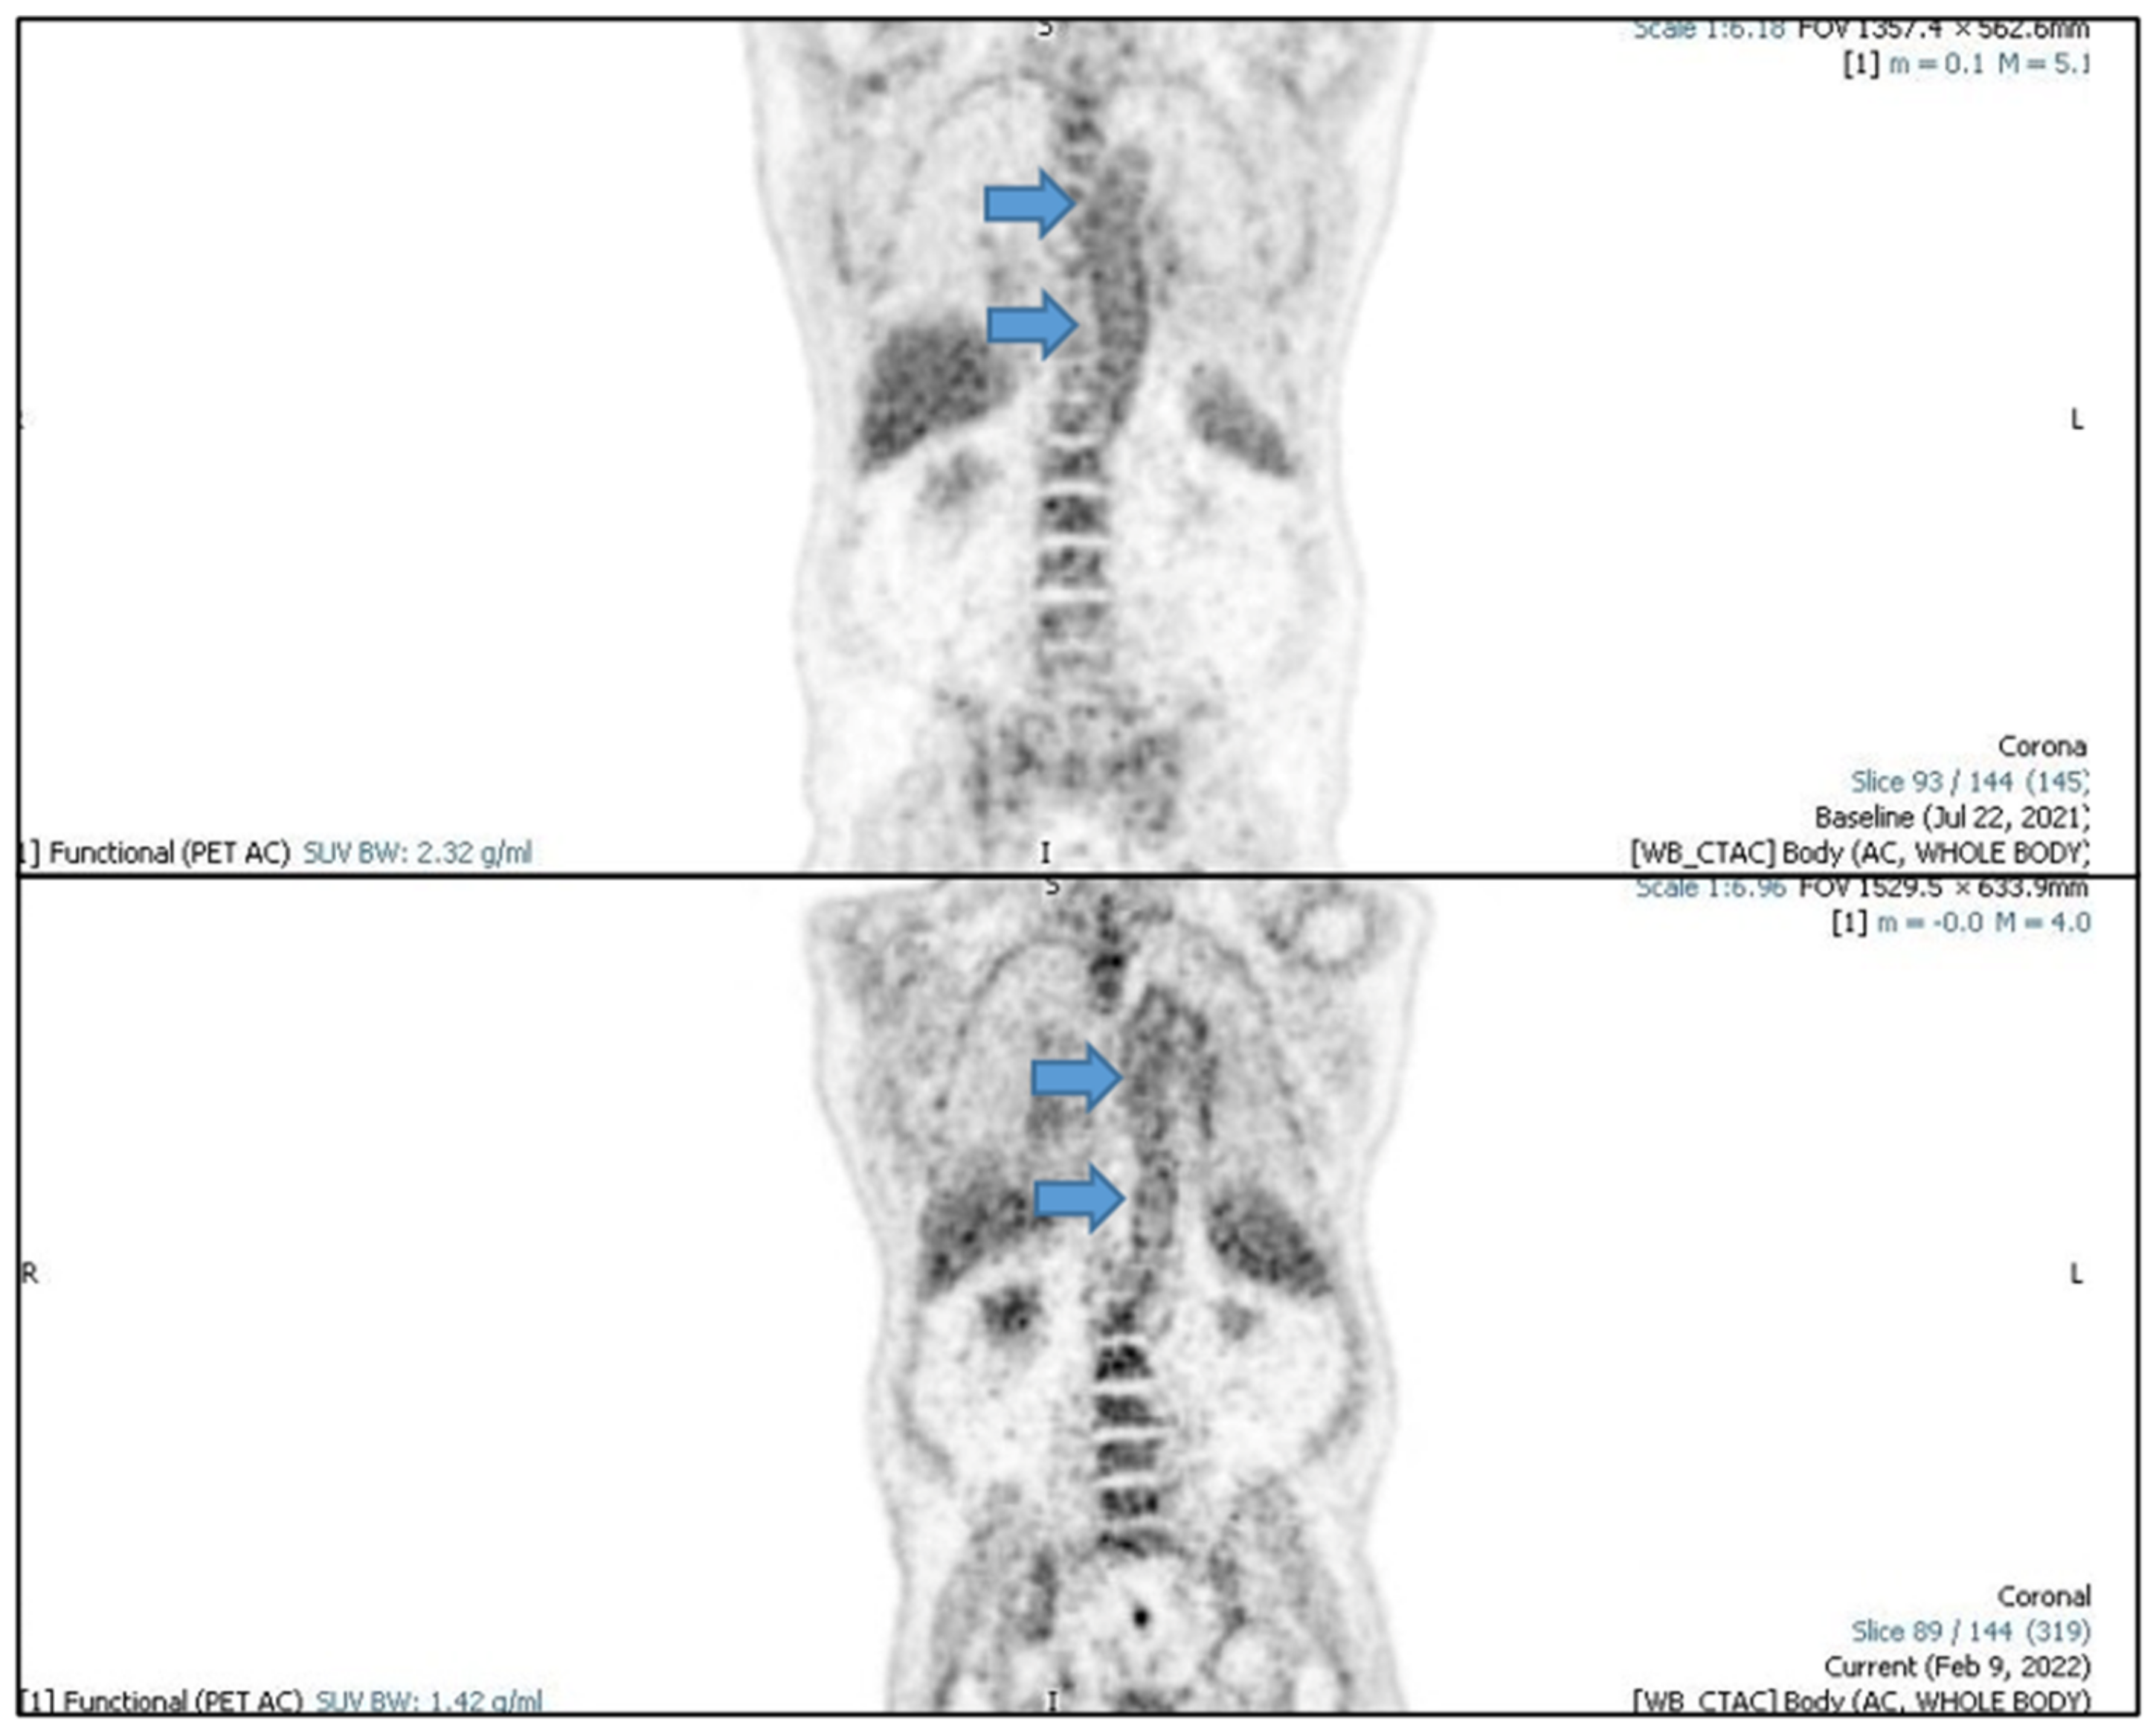

2. Case Report